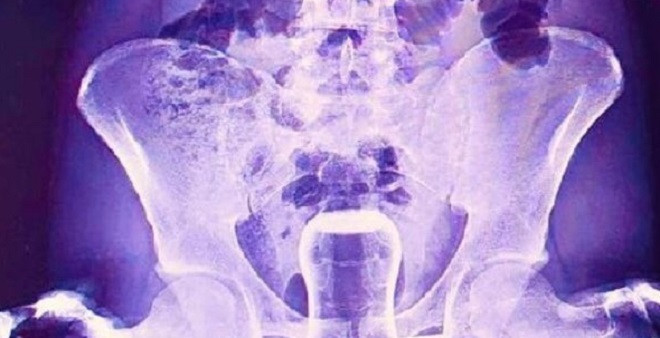

Şanlıurfa’da yaşayana bir olay şoke etti. Basur hastası olduğu belirtilen bir hastan hacamat yaptırmaya karar verdi. İsmi açıklanmayan hastaya hacamat yapılırken yağlı çay bardağı anüsüne kaçtı. Çaresiz kalan hasta soluğu hastaneden aldı.

Mehmet Akif İnan Eğitim ve Araştırma Hastanesine kaldırılan hasta doktorlar tarafından ameliyata alındı. Hastanın anüs bölgesindeki bardak doktorlar tarafından çıkartıldı.